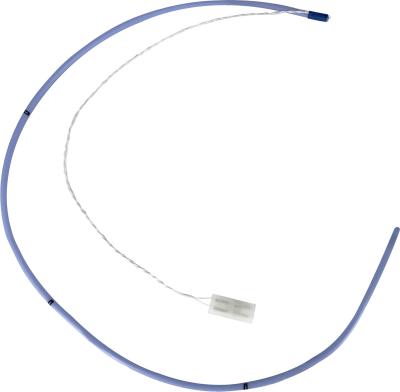

5mW Ntc 5k Thermistor , Low noise iR temperature sensor For intestine

High Light:5k intestine ir temperature sensor, Low Noise ntc 5k thermistor, 5mW ir temperature sensor

5K 10K Medical Temperature Sensor Application Medical Equipment According to application, medical temperature sensor will be grouped into 3 types: body surface temperature sensor, body cavity temperature sensor and disposable body temperature sensor. Body surface temperature sensor is used to measur... View More